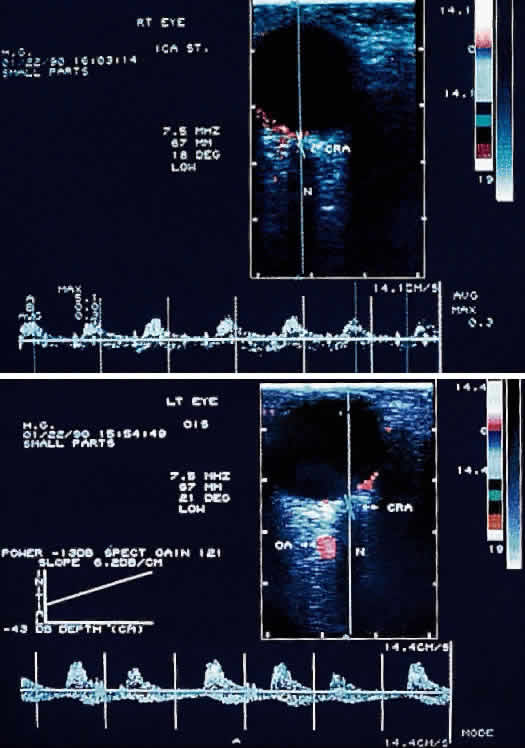

Prolonged arm-to-retina circulation times are frequently observed (Fig. 3B).24 This reflects the slower flow of blood from the carotid artery to the central retinal artery due to carotid occlusive disease. In normal persons, fluorescein dye is first detected in the retinal vasculature 12 to 15 seconds after dye is injected into the arm vein. Uncommonly, dye may take up to 20 seconds to reach the retinal arteries in a normal person. In ocular ischemic syndrome, arm-to-retina circulation times well over 20 seconds are not uncommon. The arm-to-choroid circulation time is also frequently prolonged in ocular ischemic syndrome because of the slow flow of blood from the carotid artery to the short posterior ciliary arteries. In pronounced cases, complete choroidal filling may still be lacking at 1 minute after injection. Accurate measurement of the arm-to-retina or arm-to-choroid circulation times requires experienced fluorescein angiography personnel, and these measurements depend on whether the dye was injected in the antecubital fossa or the hand, the rate of injection, and a reliable timer start time. Delayed or patchy choroidal filling may be seen in 60% of eyes affected with ocular ischemic syndrome (see Fig. 3B; Fig. 3C).1 Normally, the choroid is completely filled within 5 seconds after the initial appearance of dye in the choroid. Patchy choroidal filling greater than 5 seconds reflects sluggish blood flow through the short posterior ciliary arteries. In some cases, one or more quadrants of the choroid may display significantly slower filling than the other quadrants, indicating a relatively lower perfusion of individual short posterior ciliary arteries. Retinal arteriovenous transit time is measured from the initial appearance of dye within the retinal arteries in the temporal vascular arcade until the corresponding veins are completely filled. In normal patients, this occurs within 11 seconds; in ocular ischemic syndrome, the arteriovenous transit time is prolonged in approximately 95% of affected eyes (see Fig. 3B and C; Fig. 3D).1 Although this finding is relatively sensitive for a retinal vascular flow anomaly, it may also be seen in other vascular occlusive disorders, such as arterial and venous occlusive disease. Sometimes, a well-demarcated, leading edge of fluorescein dye within a retinal artery may be seen (Fig. 4B and C). This distinctly abnormal finding is seen in retinal arterial occlusion and ocular ischemic syndrome. In extreme cases of ocular ischemic syndrome, the retinal veins may fail to fill throughout the entire study. Staining of the retinal vessels can be seen in approximately 85% of ocular ischemic syndrome eyes in the later phases of fluorescein angiography (Figs. 4E, 5C, and 6C).1 The arterioles are usually involved to a greater extent than the venules. Hypoxic damage to the endothelial cells and pericytes may account for this phenomenon.11,25 In contrast to ocular ischemic syndrome, fluorescein angiography of eyes with central retinal artery obstruction rarely show late vascular staining. In CRVO, the retinal veins typically stain more than the retinal arteries.